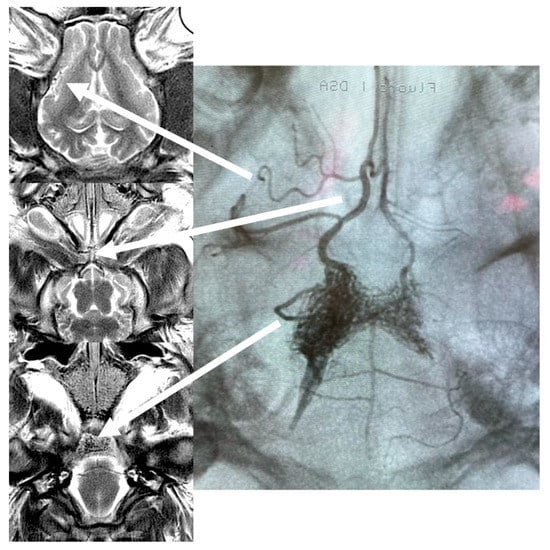

DSA run confirmed the filling of the RM and right-sided intracranial ICA, MCA, and ACA with slight reflux to the left side and posterior circulation (Figure 1).

Figure 1.

Test infusions through Apollo microcatheter under (A) X-ray and (B) real-time dynamic EPI-GRE MRI monitoring—dynamic images available in the Supplementary Material Video S1.

After the series of anatomical T1 and T2 sequences, a dynamic gradient-echo (GE)—echo-planar imaging (EPI) scan was used to monitor microcatheter injection in real-time. Test infusion of diluted gadolinium (10 mM) was seen as a short wash-in and wash-out of hypointense signal, confirming the proper position of the microcatheter and verifying the area of trans-catheter perfusion (Supplementary Material Video S1). After filing the dead space of Apollo with 0.3 mL of DMSO, 3 mL of Onyx 18 (Medtronic) was injected.

Onyx propagation was observed in real-time with initial ipsilateral RM filling followed by some main cerebral arteries and their branches distribution. The relatively bright signal within RM and the brain prior to Onyx injection provided a good background for the dark, low signal of the embolic agent spreading in rete mirabile and small brain arteries. (Supplementary Material Video S2/Figure 2).